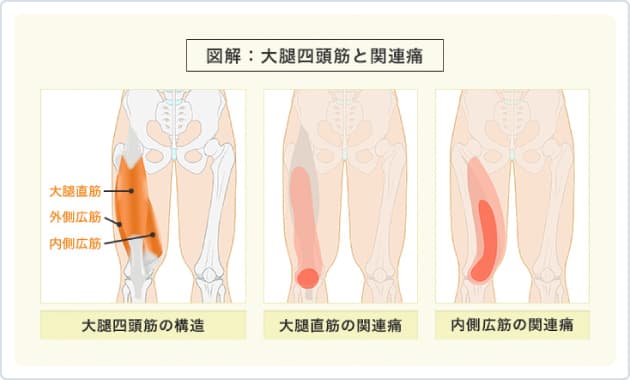

下記図は膝を安定させるために大いに働く大腿四頭筋という筋肉にトリガーポイントが発生した際に痛みの出る範囲です。図からもわかるように膝の内側などを中心に痛みを感じます。※専門用語で関連痛と言います。